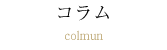

出っ歯とは?上顎前突の特徴と口ゴボ(上下顎前突)との違い

出っ歯は、主に上の前歯(中切歯)が前方に傾いている状態を指します。医学的には「上顎前突(じょうがくぜんとつ)」と呼ばれ、歯の生え方や顎の骨の大きさのバランスによって引き起こされることが多いです。

口ゴボとの違い

口ゴボと出っ歯は似ていますが、出っ歯は「前歯の傾き」によるものが大きく、口ゴボは「上下の顎全体の突出」が原因であることが多いです。そのため、矯正治療の方法も異なることがあります。